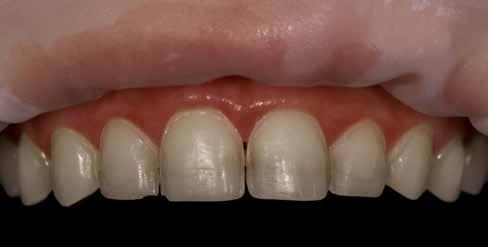

A fogászati kezelések során manapság már nem kizárólag az esztétikai megjelenés helyreállítására törekszünk. Sokszor a kedvezőtlen esztétikai megjelenés hátterében álló okok következményes módon a fogazat funkcionális működését is károsítják, így a kezelések során ezeknek a helyreállításával is foglalkoznunk kell. A különböző funkcionális és esztétikai diszkrepanciák kezelésére számtalan módszer létezik, ám ezen fogászati beavatkozások mindegyikében közös, hogy a kivitelezésük során nagyon szoros együttműködésre van szükség a kezelést végző fogorvos és a munkáját segítő fogtechnikus között. Az alábbi esetbemutatás során egy fiatal hölgypáciens fogazatának héjak alkalmazásával történő esztétikai és funkcionális rehabilitációját szeretnénk ismertetni.

A kezelés során az jelentette a legnagyobb kihívást, hogy a héjakkal ellátott fogak élethűen utánozzák a természetes fogazat megjelenését. A fogpótlás színének, valamint a restaurátumok felszíni textúrájának és alakjának harmonikusan kell a páciens arcesztétikájához és karakteréhez illeszkednie.

A tényleges protetikai ellátás megkezdése előtt a páciens mosolygás közben látható fogait otthoni fogfehérítés keretei között a kérésének megfelelő A1-es fogszín eléréséig fehérítettük. A fehérítés során a későbbiekben héjakkal ellátásra kerülő fogak színén nem változtattunk. A fogak előkészítése részeként csupán a két felső nagymetsző (1.1,2.1) incizális élét kellett kismértékben redukálni. A többi felső front fog (1.3,1.2,2.2,2.3) nem került preparálásra.

A héjak átadását követően kialakuló állapot valósághű módon történő bemutatása érdekében próbapasztát alkalmaztunk (Try-In-Paste; Variolink® Esthetik Try-In-Paste, Ivoclar Vivadent) (11. ábra). A próba során ellenőrizzük a héjak színét, formáját és transzparenciáját. A próbapaszta alkalmazásának egyik lényeges pontja, hogy a paszta színe egyezzen meg a végleges beragasztás során alkalmazni kíván ragasztóanyag színével. A héjak végleges rögzítése során mindig adhezív rendszereket használunk.

nak megfelelően – előkészítjük (orthofoszforsavval történő savazás, lemosás, szárítás és bond réteggel történő fedés). Ezzel egyidejűleg a ragasztásra kerülő héjak is előkészítésre kerülnek (hidrofolysavval történő savazás, lemosás, szárítás, szilanizálás, bond réteggel történő fedés, és végül az alkalmazni kívánt ragasztóanyag felvitele). Ezután a héjakat a fogak felszínén egyesével pozicionáljuk, majd néhány másodpercen keresztül polimerizációs lámpa segítségével megvilágítjuk. Ezt követően a kifolyó ragasztófelesleget eltávolítjuk, majd elvégezzük a restaurátumok végső polimerizálását. A héjak végleges rögzítését követően az esetlegesen visszamaradt ragasztómaradványok eltávolításra kerülnek, valamint ellenőrizzük az okklúzió és artikuláció közben létrejövő fogérintkezéseket. Az optimális esztétikai eredmény biztosítása érdekében kiemelt jelentősége van a papillák helyreállításának (rózsaszín esztétika). A modern fogorvoslás egyik kiemelt célja a fehér- és rózsaszín esztétika közti harmonikus egyensúly megteremtése. A papillák színe, nagysága és szimmetrikus megjelenése meghatározó szerepet tölt be a rózsaszín esztétika kialakításában. Az íny lefutása ugyancsak rendkívül jelentős mértékben befolyásolja a páciens fogazatának esztétikus megjelenését.

A cikkünkben bemutatásra kerülő eset ellátása során preparációt nem igénylő héjak készítése mellett döntöttünk. A héjak készre vitele során a platinafólia technikát alkalmaztuk. Annak ellenére, hogy az elkészítésre kerülő héjak rendkívül vékonyak, és ezáltal a végleges rögzítésük előtt jelentős törésveszéllyel állunk szemben, összességében mégis olyan minimál invazív kezelési eljárásnak számítanak, amely segítségével kifogástalan esztétikai eredményeket lehet elérni. A fent leírtak alapján bátran javasoljuk e módszer alkalmazását.